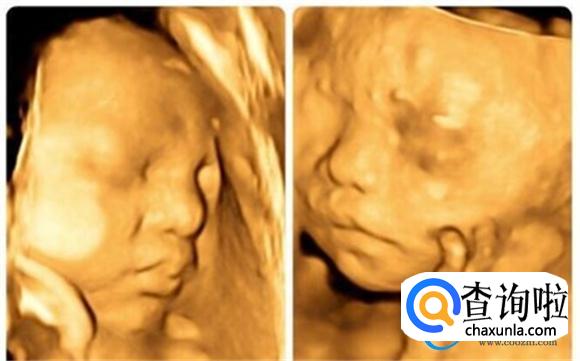

四维彩超技术在现代医学中应用广泛,尤其在孕期检查中,可以帮助孕妈妈们更全面地了解未出生的胎宝宝的生长发育状态和活动变化。通过四维彩超,可以观察到胎宝宝的实时动态画面,包括身体躯干、器官活动以及性别等信息。四维技术的到来,可以使得我们可以多维度、多角度、多方位地了解、观察到母体中胎宝宝的生长发育状态和活动变化的。同时,也有助于早期发现一些胎宝宝的先天性疾病,提供了很有力的科学依据。

对于很多孕妈妈们来说,想要早点知道胎宝宝的长相、面部、身体的轮廓、结构如何,这都是很正常的事情。而四维超声技术可以帮助孕妈妈们实现这个愿望。孕期时的四维打印的胎宝宝的照片和出生后的宝宝的长相和各种体态基本上是相一致的。由于四维超声技术的稳定性,宝宝的五官位置还有各个具体的躯干样子都是在四维彩超下看的一清二楚的。因此,孕妈妈们不必过于担心。